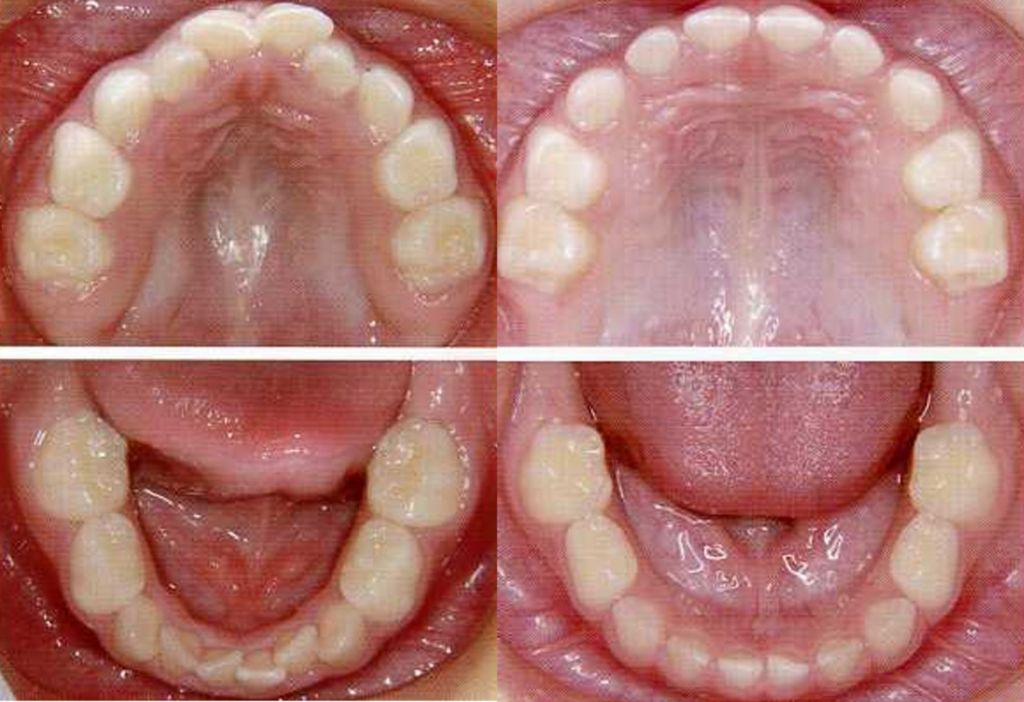

- 左:さんかくの顎

- 右:まるい顎

文字通り、お口の成長において「左側の成長が△」で「右側の成長が◯」です。乳歯列期のすきっ歯は、ほぼ問題ありません。そうでなければ、乳歯より大きな永久歯は並べません。

まるい顎とさんかくの顎

資料の左側のまぁるい顎が理想的に育った顎です。右側のV字のような三角形に近い形の顎は少々問題を抱えて成長している顎です。これは将来的に矯正治療が必要になる可能性を示すサインです。

一番上の抱っこの写真は、まるい顎やさんかくの顎に育つ過程の一例です。下の写真では「歯がきれいに揃いそう」や「歯並び悪くなりそう」は一目瞭然ですね。